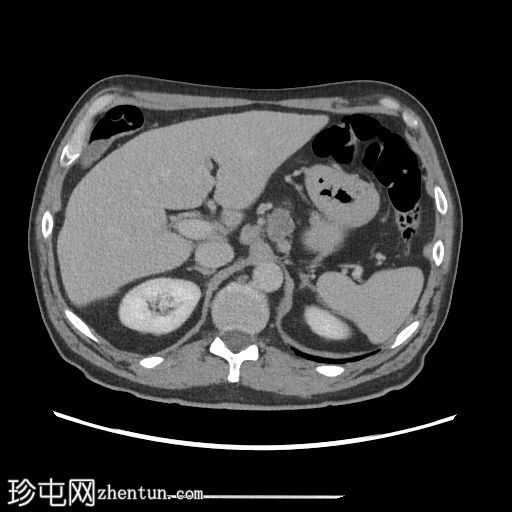

冠状位增强扫描(门静脉期)

食管周围、隆突下及气管旁可见多个肿大淋巴结。左侧食管上段旁、气管食管沟处可见一个远处巨大淋巴结,可能影响左侧喉返神经

冠状位图像再次显示巨大淋巴结,并证实右侧声带代偿性向内侧弯曲。

喉前囊性病变外观良性。